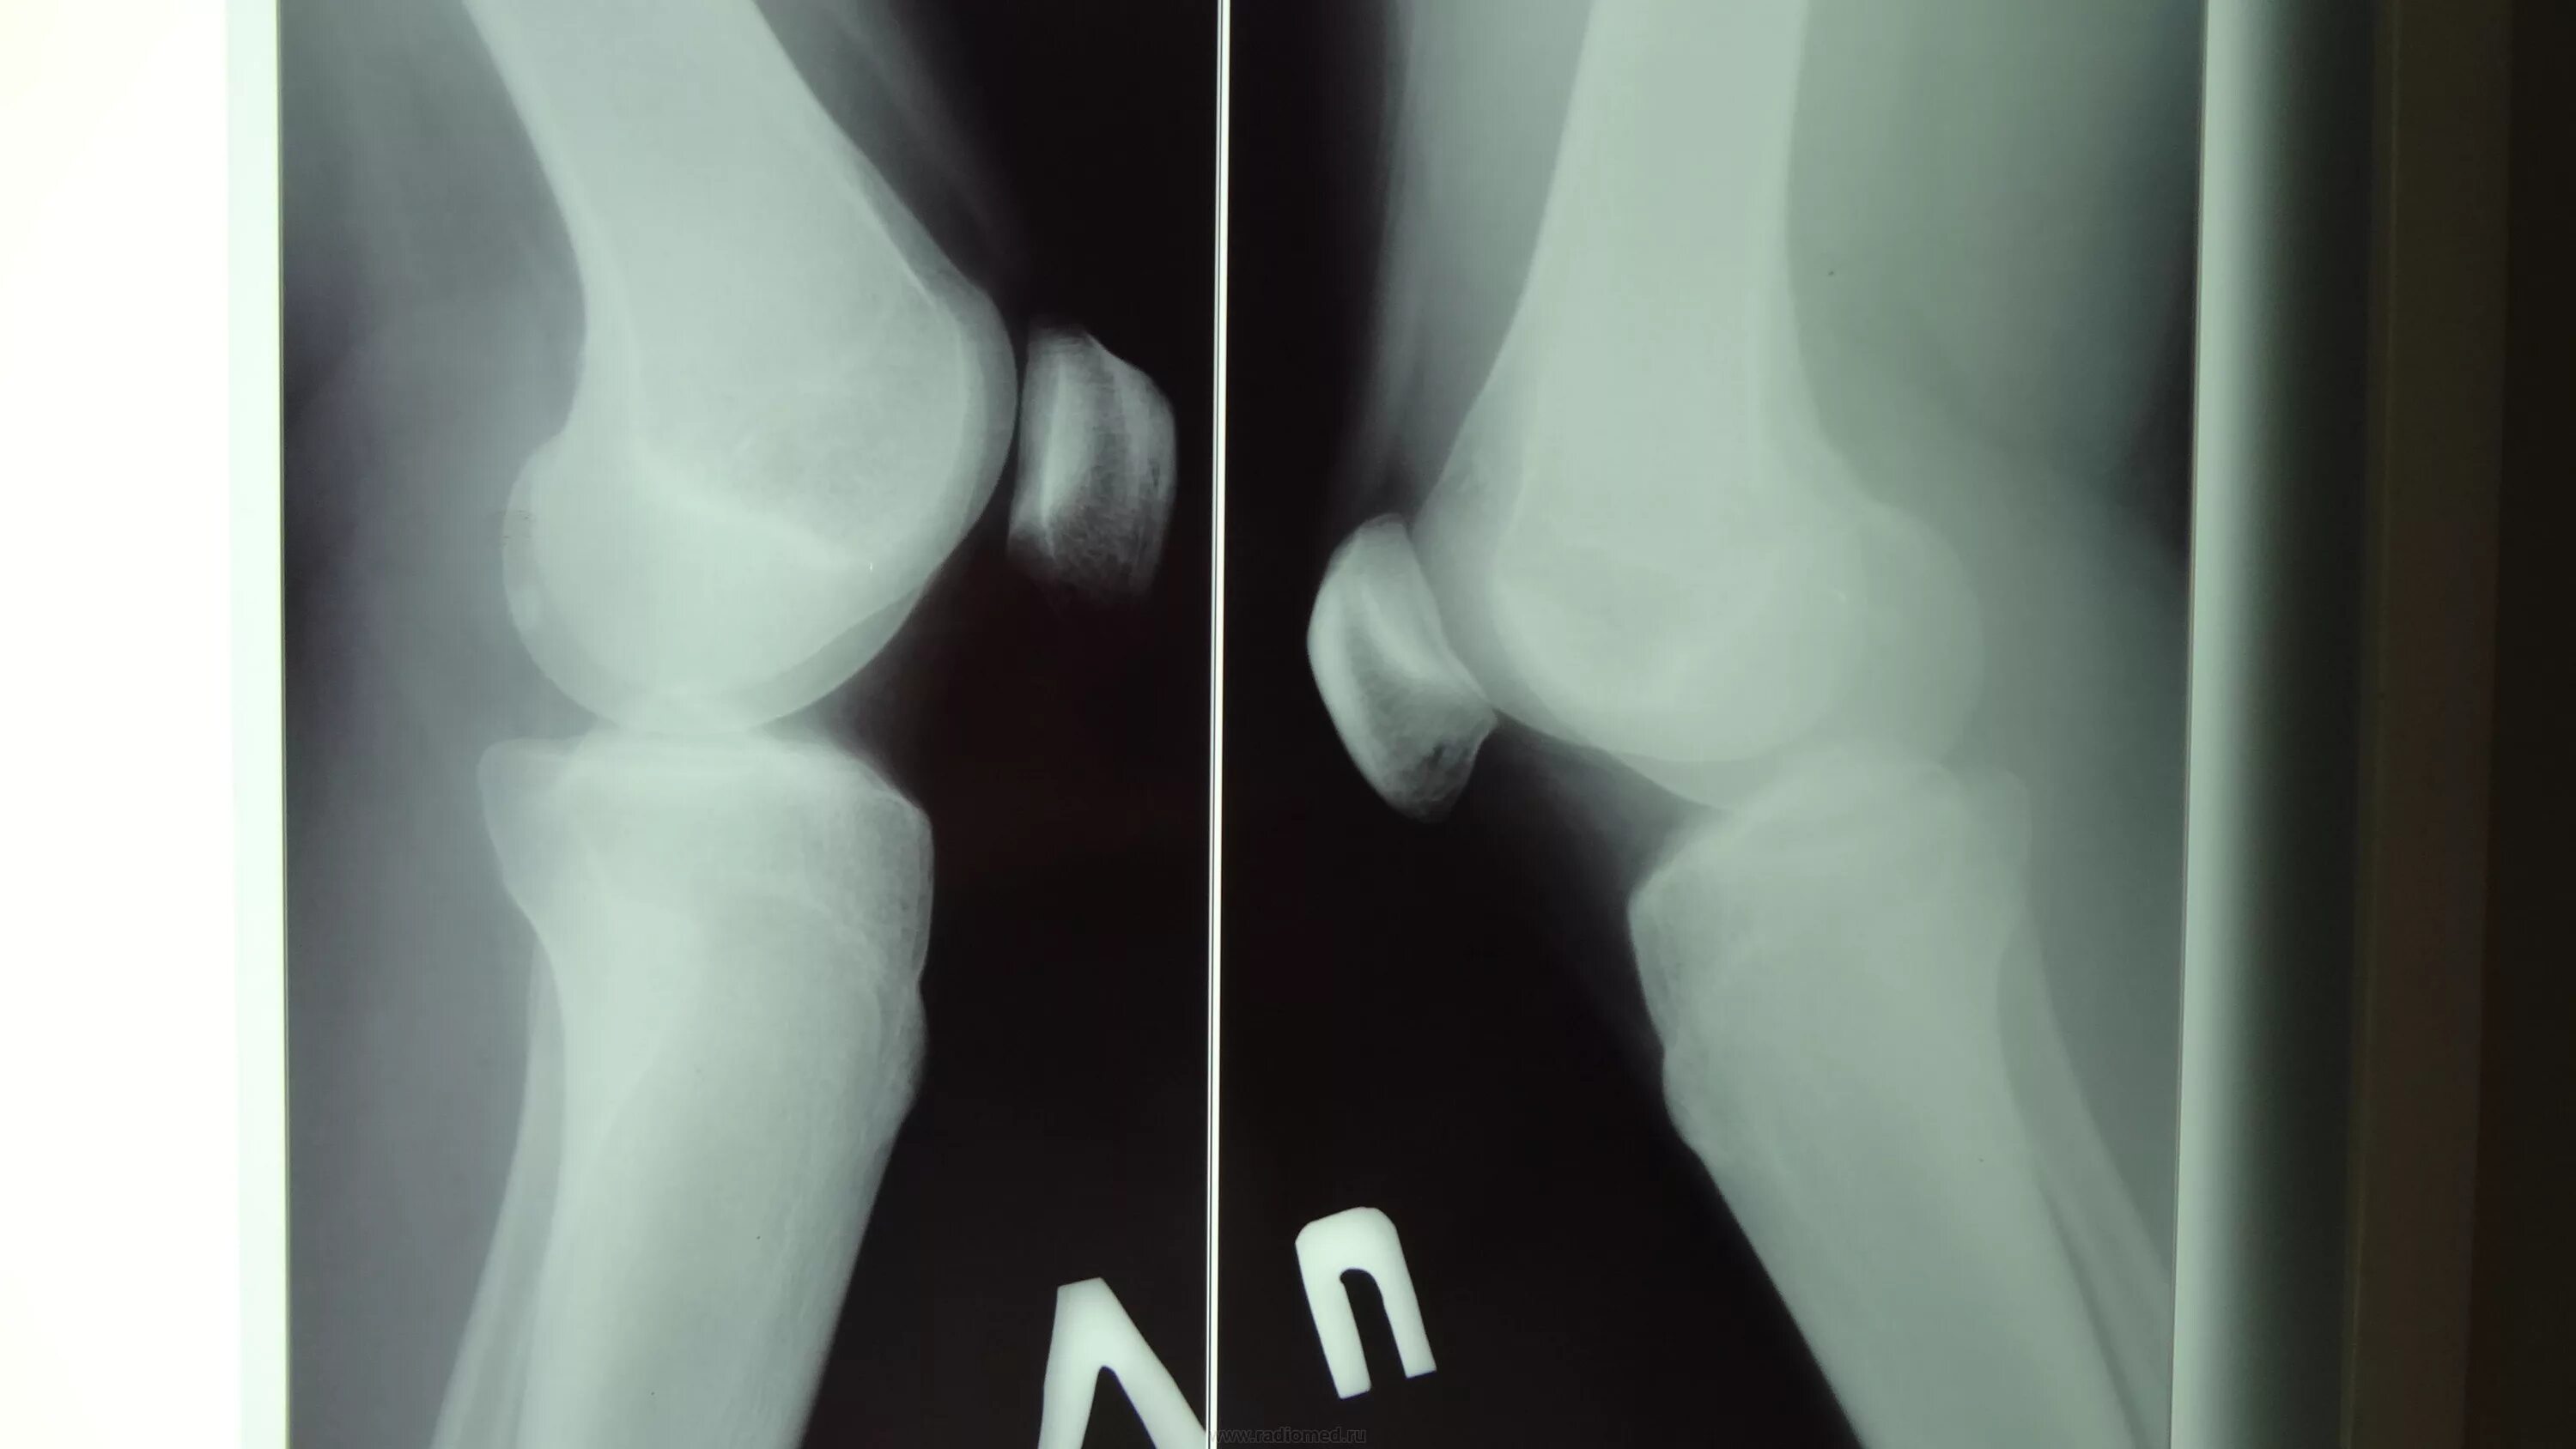

Болезнь шляттера код по мкб